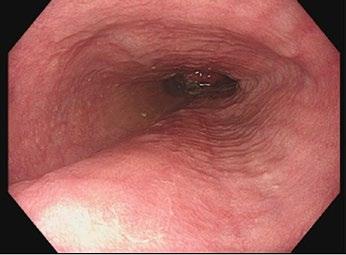

This edition also addresses the unintended consequences of medical interventions in elite sport. Dr Christopher Mogekwu presents a cautionary and educational case in “A Bitter Pill to Swallow: Doxycycline-Induced Oesophagitis in an Elite Athlete”, reminding practitioners of the importance of vigilance, communication, and player education when prescribing commonly used medications.

53 A Bitter Pill to Swallow: Doxycycline-Induced Oesophagitis in an Elite Athlete

Dr Chris Mogekwu